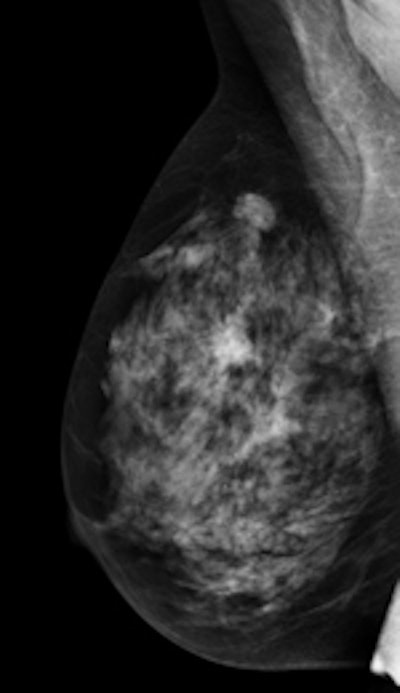

Left: Mediolateral oblique view of a patient with two malignant masses (invasive ductal carcinomas) using mammography. Center: Same patient viewed via craniocaudal mammography. Right: Same patient viewed on DBT. The spicules and tumor structures are better depicted by DBT. Copyright Dr. Gisella Gennaro.

Left: Mediolateral oblique view of a patient with two malignant masses (invasive ductal carcinomas) using mammography. Center: Same patient viewed via craniocaudal mammography. Right: Same patient viewed on DBT. The spicules and tumor structures are better depicted by DBT. Copyright Dr. Gisella Gennaro."Manufacturers are now progressively moving from prototype systems to clinical products, and exposure control is being optimized, allowing the acquisition of a DBT view at the same dose as a single mammography view," the authors noted. "This would permit use of a combined technique, like the one proposed in this work, at the same dose level as the reference standard (two-view digital mammography), with some benefits in terms of clinical performance, or, alternatively, use mediolateral oblique-view DBT alone at comparable performance to that of two-view mammography, but at half the breast dose."